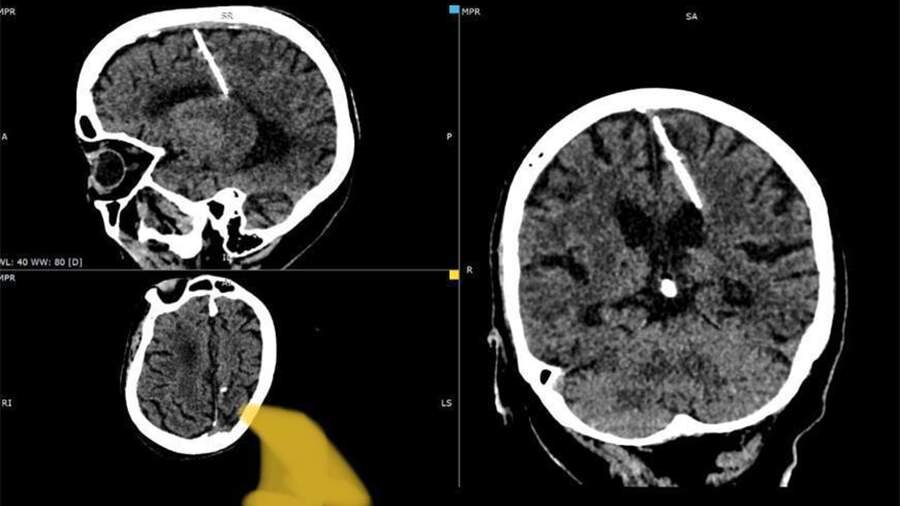

В мозгу пенсионерски на Сахалине обнаружили трехсантиметровую иглу

Фото: Минздрав Сахалинской области

Иглу нашли в левой теменной доле, тем не менее, это не привело к «ожидаемым последствиям» и девочка осталась жива, пояснили в минздраве. Женщина рассказала, что по жизни ее никогда не мучили головные боли, а инородное тело обнаружилось в этом году во время проведения компьютерной томографии.